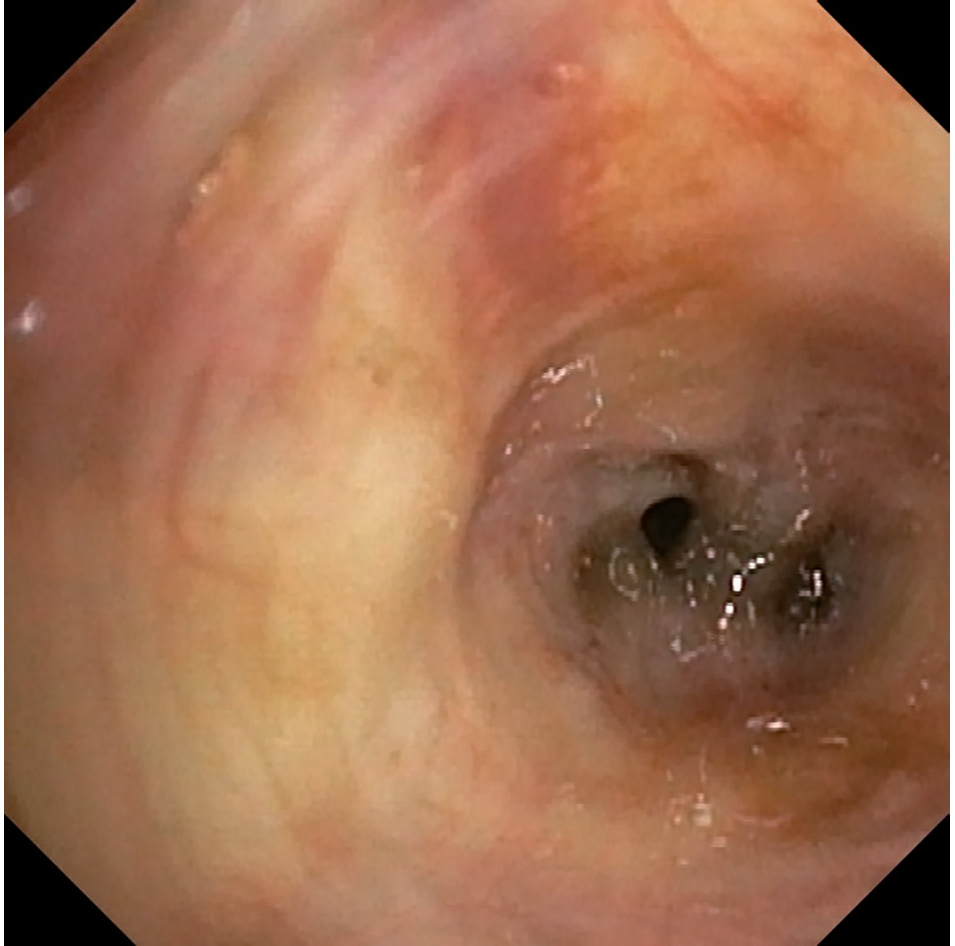

Выполнена фибробронхоскопия. Просвет трахеи широкий, свободный, хрящевые кольца хорошо контурируются, слизистая розовая, блестящая, карина острая, подвижная. Правое легкое: осмотру доступны бронхи до субсегментарных – устья их свободные, шпоры острые, подвижные. Слизистая несколько гиперемирована. Левое легкое: бронхиальное дерево проходимо до сегментарных бронхов. Устья всех доступных бронхов свободные, шпоры острые, подвижные. Слизистая гиперемирована, местами прожилки крови. В одном из субсегментарных ветвей В1/2 слизистая рыхлая, серого, а местами черного цвета, диффузного характера, в просвете виден сгусток черного цвета. Эндоскопическая картина крайне подозрительная на метастаз меланомы. Произведена браш-биопсия и смывы (рис. 1).

Рис. 1. Пациент Р. 67 лет. Фибробронхоскопия. ЭБМ меланомы верхней доли левого легкого

Fig. 1. Patient R., 67 years old. Fibrobronchoscopy. Endobronchial metastases of melanoma in the upper lobe of the left lung.

В представленном нами наблюдении у больного при бронхоскопии выявлена диффузная инфильтрация слизистой черного цвета субсегментарных ветвей бронхиального дерева слева B1/2. Выполнена браш-биопсия. При цитологическом исследовании материала пациента установлена эпителиоидноклеточная пигментная меланома. В связи с этим мы считаем, что наличие черной пигментации слизистой бронхов локального или диффузного характера свидетельствует о специфическом эндобронхиальном поражении меланомы.

При подозрении на ЭБМ бронхоскопия – оптимальный метод визуализации, позволяющий оценить распространенность опухолевого процесса, а также получить морфологическое подтверждение диагноза. Каких-либо специфических эндоскопических признаков поражения бронхов при меланоме нет. Однако черная пигментация слизистой бронхов очагового или диффузного характера свидетельствует о поражении меланомой.